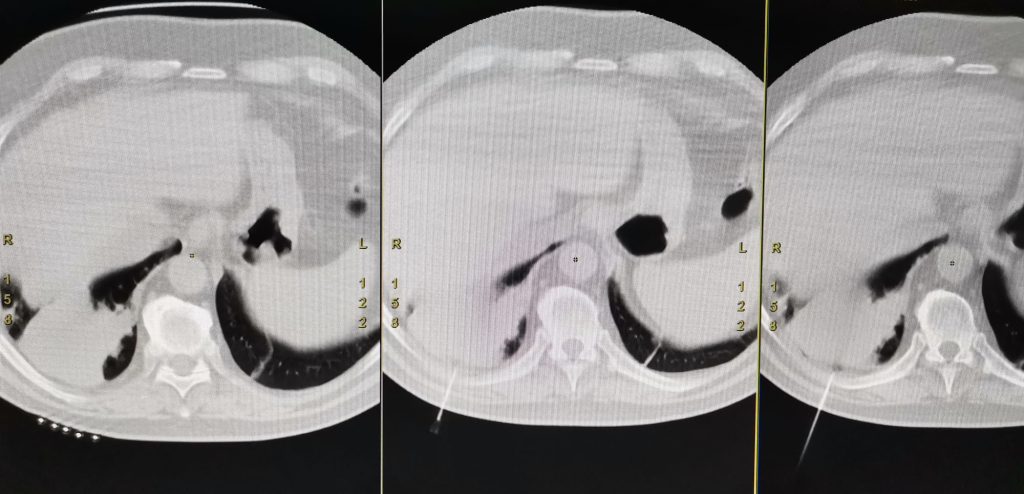

Acest tip de biopsie este o intervenție minim invazivă care permite recoltarea, cu ajutorul unui ac de biopsie, a unui fragment de țesut dintr-o formațiune suspectă imagistic, sub ghidaj CT. Metoda este utilă pacienților cu formațiuni pulmonare neoplazice din Spitalul Clinic Județean de Urgență, pacienților din celelalte spitale din județul Sibiu, dar și din județele limitrofe.

Intervenția, realizată în premieră la SCJU Sibiu, a fost posibilă datorită modernizării Laboratorului Clinic de Radiologie cu aparatură de înaltă performanță achiziționată din fonduri europene atrase de spital printr-un proiect POIM.